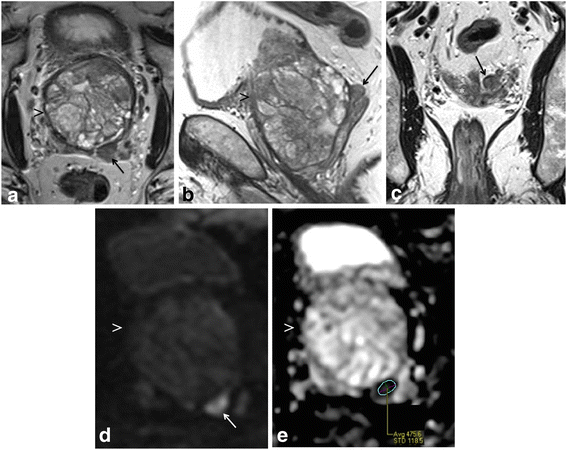

Multi-parametric prostate MR imaging revealed no abnormality in the central, transitional or peripheral zones of the prostate gland. However, in the left seminal vesicle and non-contiguous with the adjacent prostate gland or capsule, there was an abnormal 1.5 × 1.2 × 1.0 cm lesion with conspicuous hypointense T2-weighted (T2W) signal intensity seen on high-resolution axial imaging (Fig. 1a). High-resolution coronal and sagittal T2W images show, to advantage, this lesion within the left seminal vesicle (Fig. 1b-c), external to the prostate gland capsule, which is maintained with normal signal intensity and morphology. No T2W signal intensity abnormality is seen in the adjacent left prostate gland base related to the left seminal vesicular abnormality. Moreover, there is no exophytic hyperplastic nodule or contiguous extension of prostatic glandular tissue related to the abnormality in the left seminal vesicle. On high b-value diffusion weighted imaging (DWI) and apparent diffusion coefficient (ADC) map, this lesion features significantly diminished diffusivity with low ADC mean value of 0.5 × 10−3 mm2/s (Fig. 1d-e). There is no abnormal diffusivity in the adjacent or regional left prostate gland base peripheral or transitional zone related to the left seminal vesicular abnormality. Pre- and post-contrast fat-saturated T1-weighted (T1W) imaging obtained prior to and following the infusion of intravenous gadolinium contrast show abnormal perfusion of this lesion (Fig. 2a-b). Abnormal perfusion pattern of this lesion is confirmed with CAD, which demonstrates early enhancement with partial washout and colorimetric stratification of ‘green’ and ‘red’: indeterminate/suspicious (‘green’) and highly suspicious (‘red’) (Fig. 2c dashed arrow and solid arrow). The hyperperfused lesion in the left central zone with highly suspicious enhancement (Fig. 2c asterisk) demonstrated relative hypointensity on T2W imaging with thin, circumscribed hypointense periphery, and no diminished diffusivity, compatible with a hyperplastic (BPH) stromal nodule that was later confirmed on MR imaging-TRUS fusion biopsy with no malignancy on tissue histopathological sampling. This lesion was reported as clinically significant cancer is highly likely to be present; it was subsequently targeted on MR imaging-TRUS software-based fusion biopsy. Repeat 14-core TRUS biopsy, supplemented with targeted MR imaging-ultrasound fusion-guidance, was performed of the prostate gland and left seminal vesicle. Ultrasound gray-scale imaging from the fusion biopsy confirms an abnormal hypoechoic lesion in the left seminal vesicle (Fig. 3).

Multi-parametric magnetic resonance (MR) imaging of the prostate gland demonstrates normal prostate gland however an abnormal lesion in the left seminal vesicle features classical imaging features of prostate carcinoma. a High-resolution axial T2-weighted (T2W) image demonstrates an abnormal 1.5 × 1.2 × 1.0 cm lesion with relative hypointensity (arrow) subjacent to an enlarged prostate gland (arrowhead). The capsule is maintained without trans-capsular extension. b–c High-resolution multi-planar T2W images in the sagittal and coronal planes show, to advantage, this lesion within the left seminal vesicle (arrow), external to the capsule of the prostate gland (arrowhead). No T2W signal intensity abnormality is in the adjacent left prostate gland base peripheral or transitional zone. Moreover, there is no exophytic hyperplastic nodule or contiguous extension of prostatic glandular tissue related to the abnormality in the left seminal vesicle. Normal right seminal vesicle denoted for comparison (asterisk). d High b-value diffusion weighted imaging (DWI) shows that this lesion demonstrates significantly diminished diffusivity (arrow). e Apparent diffusion coefficient (ADC) map confirms significantly diminished diffusivity in this lesion (arrow) with low ADC mean value of 0.5 × 10−3 mm2/s (region of interest). No diminished diffusivity was seen in the prostate gland (arrowhead)